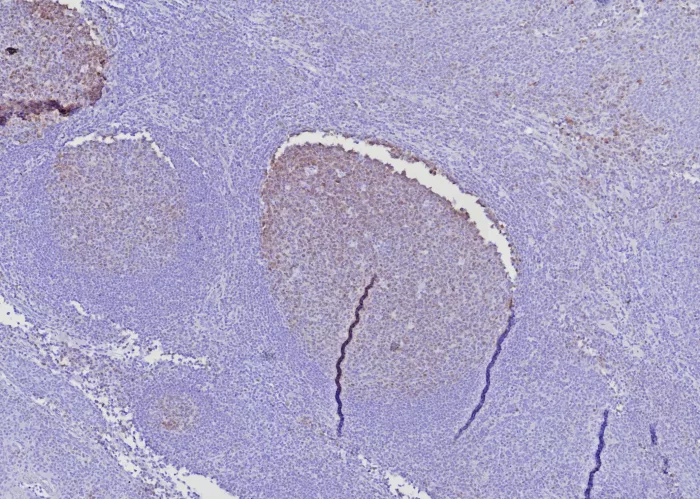

Formalin-fixed, paraffin-embedded human tonsil stained with BOB1 Mouse Monoclonal Antibody (BOB1/7468). HIER: Tris/EDTA, pH9.0, 45min. 2°C: HRP-polymer, 30min. DAB, 5min.

Formalin-fixed, paraffin-embedded human tonsil stained with BOB1 Mouse Monoclonal Antibody (BOB1/7468). HIER: Tris/EDTA, pH9.0, 45min. 2°C: HRP-polymer, 30min. DAB, 5min.